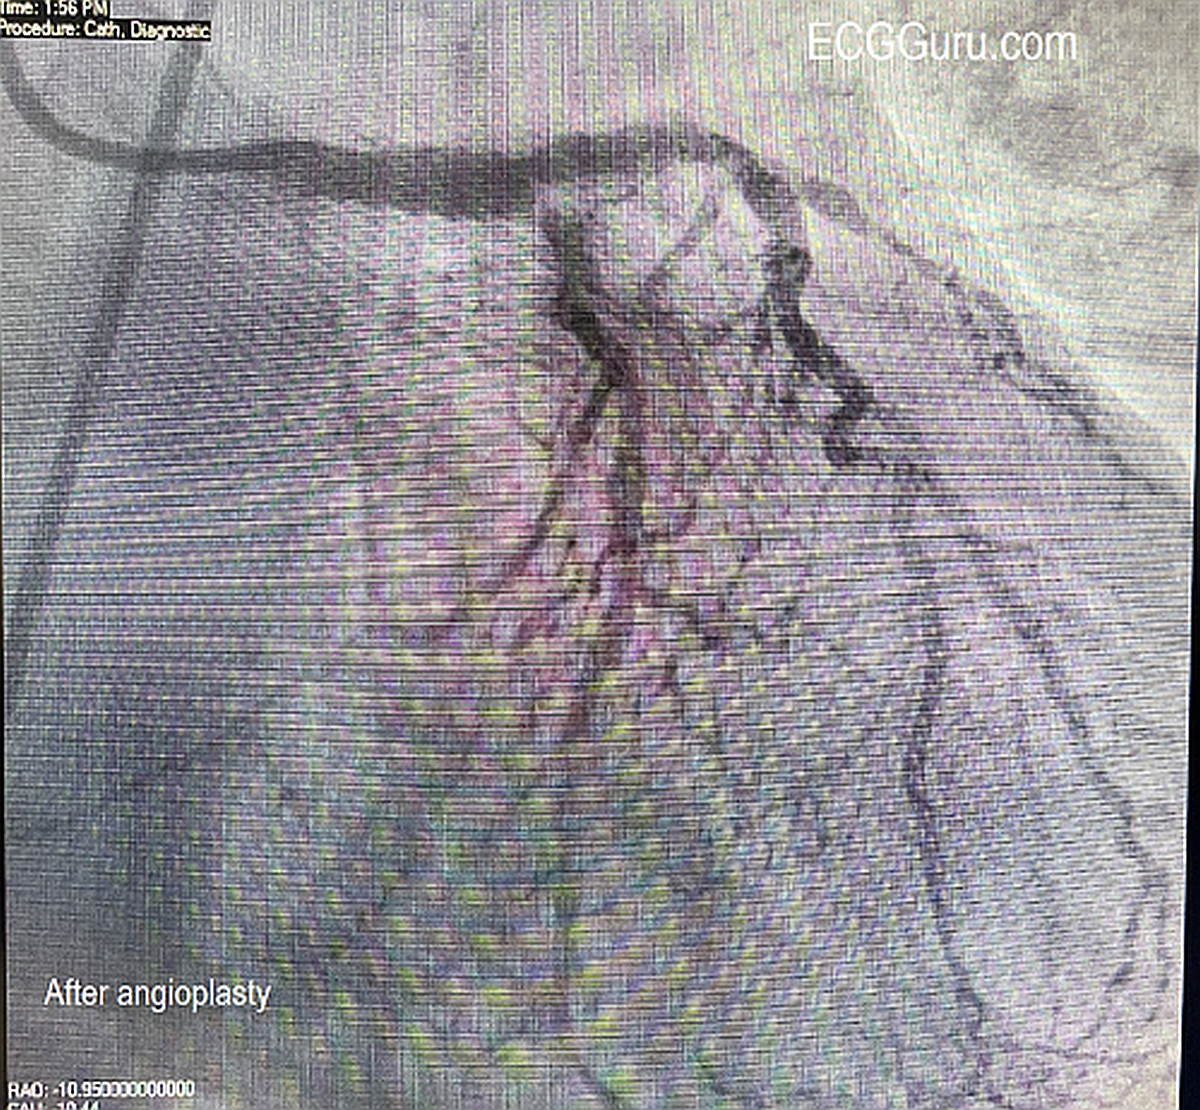

Instructors' Collection ECG: Acute Occlusive Myocardial Infarction With Cardiogenic Shock

The Patient:  67-year-old man complaining of chest pain radiating to his jaw, 10/10. He is short of breath and diaphoretic. We do not know his BP, just that it was low.  The patient states “no past medical history – never hospitalized”. He thought himself to be very healthy.  He was given aspirin 325 mg and transported to a full-service cardiac hospital as a “cardiac alert”.

The rhythm is atrial fibrillation with a rapid ventricular response (about 134/min.). The QRS width is .118 seconds (118 ms).  The frontal plane axis is slightly to the left, but WNL. The R wave progression mostly normal, but V4 is incongruous.  V2 and V3 have a tall R wave, possibly representing a pathological Q on the posterior side.  There are ST CHANGES in every lead. ST elevation is noted in III, aVF, aVR, V5 and V6, representing ischemia in the inferior wall. There is ST depression in all other leads, indicating widespread subendocardial ischemia and/or acute reciprocal depression.  Interesting that Lead II would normally be elevated when III and aVF are, but aVR is elevated, causing reciprocal ST depression in Lead II.  So, Lead II looks almost normal.

The pattern of ST elevation in aVR with widespread ST depression can indicate:

1)     Proximal occlusion of LAD or significant stenosis of Left Main artery.